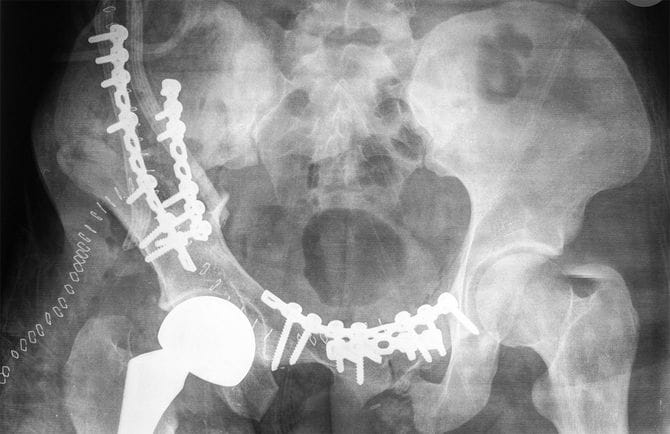

深戸さんは、母親が2015年に人工股関節置換手術を受けており、身体障害者となっていたのは知っていたが、何級かまでは把握しておらず、介護認定を受けていたことも知らなかった。